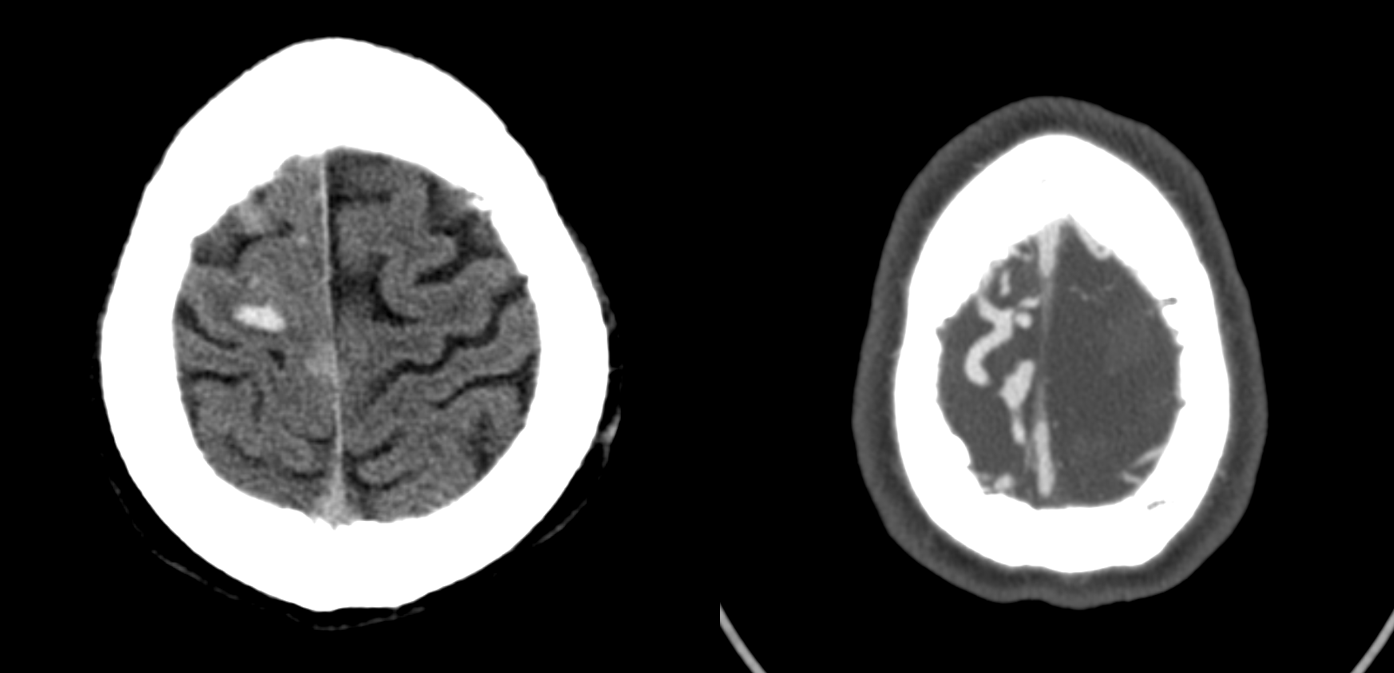

Lots of learning points here. Presentation with hemorrhage

Angio — the good side

Bad side